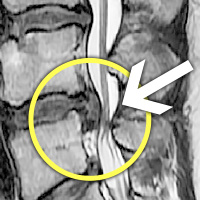

MRI ġ

ȯڰ ġı

ȸŰ渶 ġ